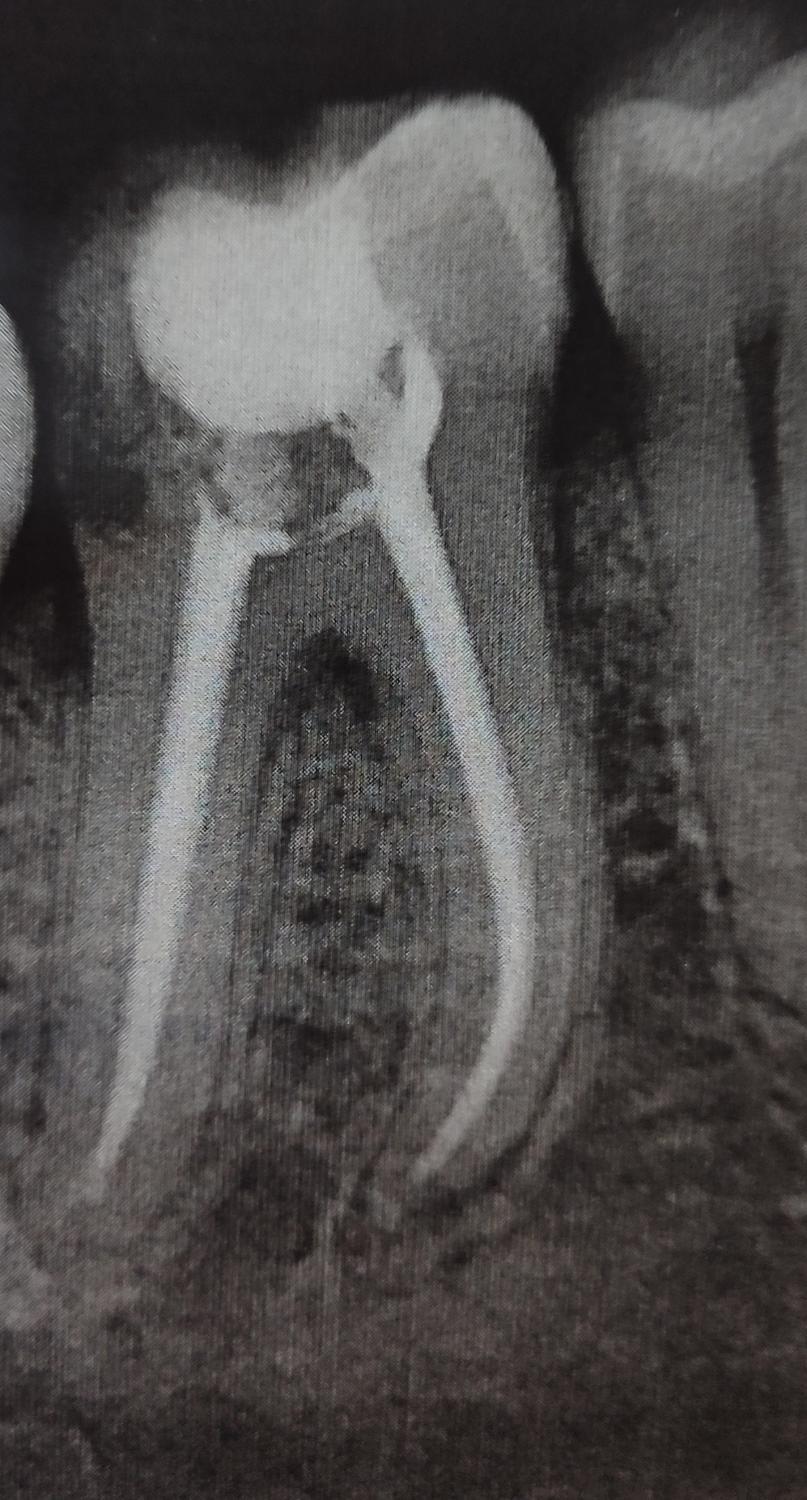

Здравствуйте. У меня такая ситуация. Откололся зуб, пошла лечить в частную клинику: нерв по снимку не нужно было удалять- стоматолог почистил кариес, постоянную пломбу поставил, нарастил зуб. Зуб неделю стал болеть. Усиливалась боль. У моего стоматолога все забито на 2 недели вперед, по острой боли пошла в другую частную клинику. После вскрытия пломбы-оказалось, что из-за некачественной прочистки кариеса развился пульпит. Пришлось удалять нерв, прочистили каналы, поставили кальций. 2 раза ходила. Поставили временную пломбу, так как стоматолог решил переделать наращивание на своих материалах. До 3 посещения еще неделя. Сейчас болит еще хуже. Прошло 6 дней после прочистки каналов и установки штифтов. Позвонила в клинику-стоматолог, говорит, по снимку все хорошо, это постпломбировочная боль.Потерпите. Поехала по острой боли в другую клинику, сделали снимок-говорит, по снимку все хорошо. Но боль адская скулу сводит, при зуб ходьбе пульсирует, стреляет в другие зубы, подчелюстная боль, в ухо стреляет. Сиду на обезболивающих, постоянно полощу,мажу гели. Что это может быть? Спасибо!